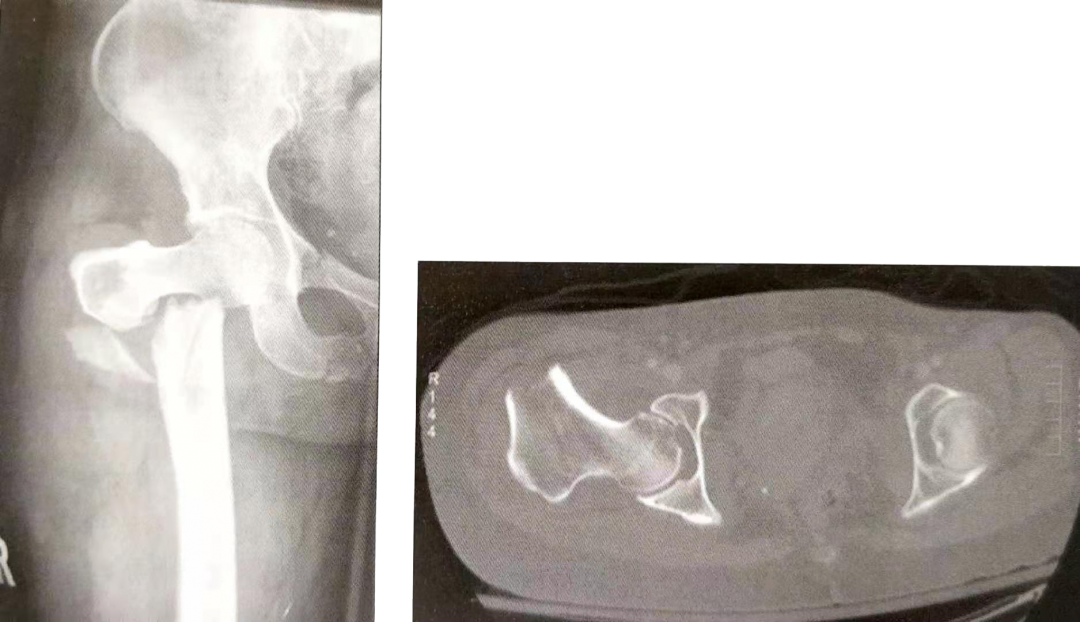

1)粉碎性转子下骨折

▲ 粉碎性转子下骨折

▲ 复杂的股骨上段骨折累及到转子下

4)股骨颈基底部和转子间骨折延伸到转子下区域

• 由于股骨颈基底骨折和粗隆间骨折不能进行桥接固定等常用的相对稳定固定方法,因此,此型骨折与单纯的转子下骨折不同。

• 滑动加压内植物对骨折区进行动态加压,但我们要选择那些对滑动距离有限制的内植物。通常在此类骨折中,股骨外侧皮质已经骨折,失去了支撑功能,如果近端骨折块无限制的滑动,会导致股骨内移。

• 仅对股骨颈基底和转子间骨折块进行锁定固定而没有加压固定,会导致骨折区应力集中,内植物失效和骨折不愈合的风险都增加。